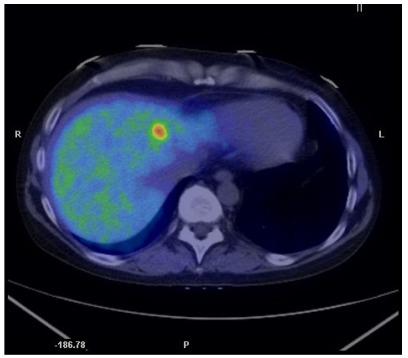

Because of the more widespread and frequent use of cross-sectional techniques, mainly computed tomography (CT), an increasing number of adrenal tumors are detected as incidental findings ("incidentalomas"). These incidentaloma patients are much more frequent than those undergoing imaging because of symptoms related to adrenal disease. CT and magnetic resonance imaging (MRI) are in most patients sufficient for characterization and follow-up of the incidentaloma. In a minor portion of patients, biochemical screening reveals a functional tumor and further diagnostic work-up and therapy need to be performed according to the type of hormonal overproduction. In oncological patients, especially when the morphological imaging criteria indicate an adrenal metastasis, biopsy of the lesion should be considered after pheochromocytoma is ruled out biochemically. In the minority of patients in whom CT and MRI fail to characterize the tumor and when time is of essence, functional imaging mainly by positron emission tomography (PET) is available using various tracers. The most used PET tracer, [(18)F]fluoro-deoxy-glucose ((18)FDG), is able to differentiate benign from malignant adrenal tumors in many patients. (11)C-metomidate ((11)C-MTO) is a more specialized PET tracer that binds to the 11-beta-hydroxylase enzyme in the adrenal cortex and thus makes it possible to differ adrenal tumors (benign adrenocortical adenoma and adrenocortical cancer) from those of non-adrenocortical origin.

由于横断面技术(主要是计算机断层扫描 [CT])的广泛和频繁应用,越来越多的肾上腺肿瘤被偶然发现(“偶发瘤”)。这些偶发瘤患者比因肾上腺疾病相关症状而进行影像学检查的患者要多得多。CT 和磁共振成像(MRI)在大多数患者中足以对偶发瘤进行特征描述和随访。在一小部分患者中,生化筛查显示功能性肿瘤,需要根据激素过度产生的类型进行进一步的诊断性检查和治疗。在肿瘤患者中,特别是当形态影像学标准提示肾上腺转移时,在排除生物化学上的嗜铬细胞瘤后,应考虑对病变进行活检。在少数 CT 和 MRI 无法对肿瘤进行特征描述的患者中,当时间紧迫时,可以使用各种示踪剂进行功能成像,主要是正电子发射断层扫描(PET)。最常用的 PET 示踪剂 [(18)F]氟脱氧葡萄糖 ((18)FDG),能够在许多患者中区分良性和恶性肾上腺肿瘤。(11)C-美托咪酯 ((11)C-MTO) 是一种更具专业性的 PET 示踪剂,可与肾上腺皮质中的 11-β羟化酶结合,从而能够区分肾上腺肿瘤(良性肾上腺皮质腺瘤和肾上腺皮质癌)与非肾上腺皮质起源的肿瘤。